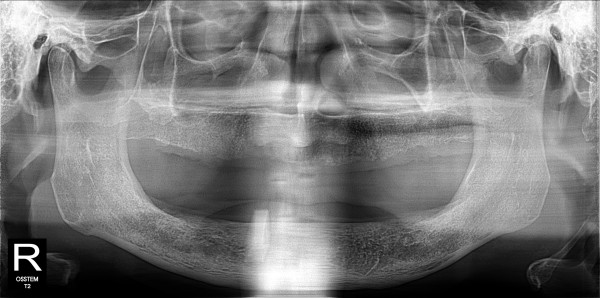

네비게이션 임플란트 최고관리자 0건 23-11-07 18:37 본문 무치악 네비게이션 임플란트 목록 이전글네비게이션 임플란트 23.11.07 다음글구치부 임플란트 23.11.07 댓글목록 0 댓글목록 등록된 댓글이 없습니다.